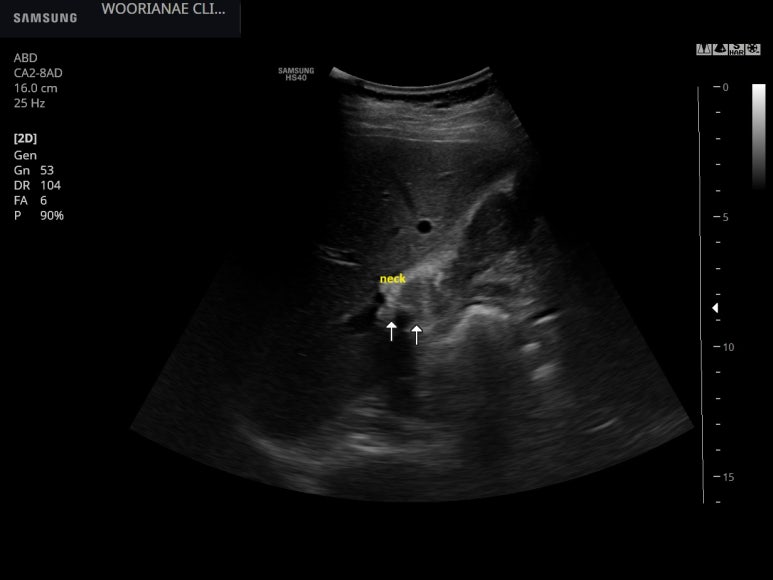

intercostal view

목에 근접해서도 박혀있는듯한 담석의 확인